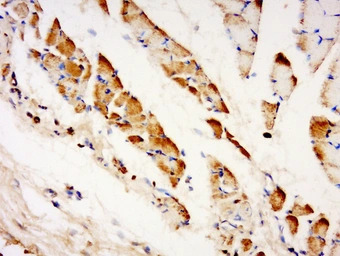

IHC-P analysis of mouse embryo muscle tissue using GTX51247 TXLNB antibody.

Dilution : 1:200